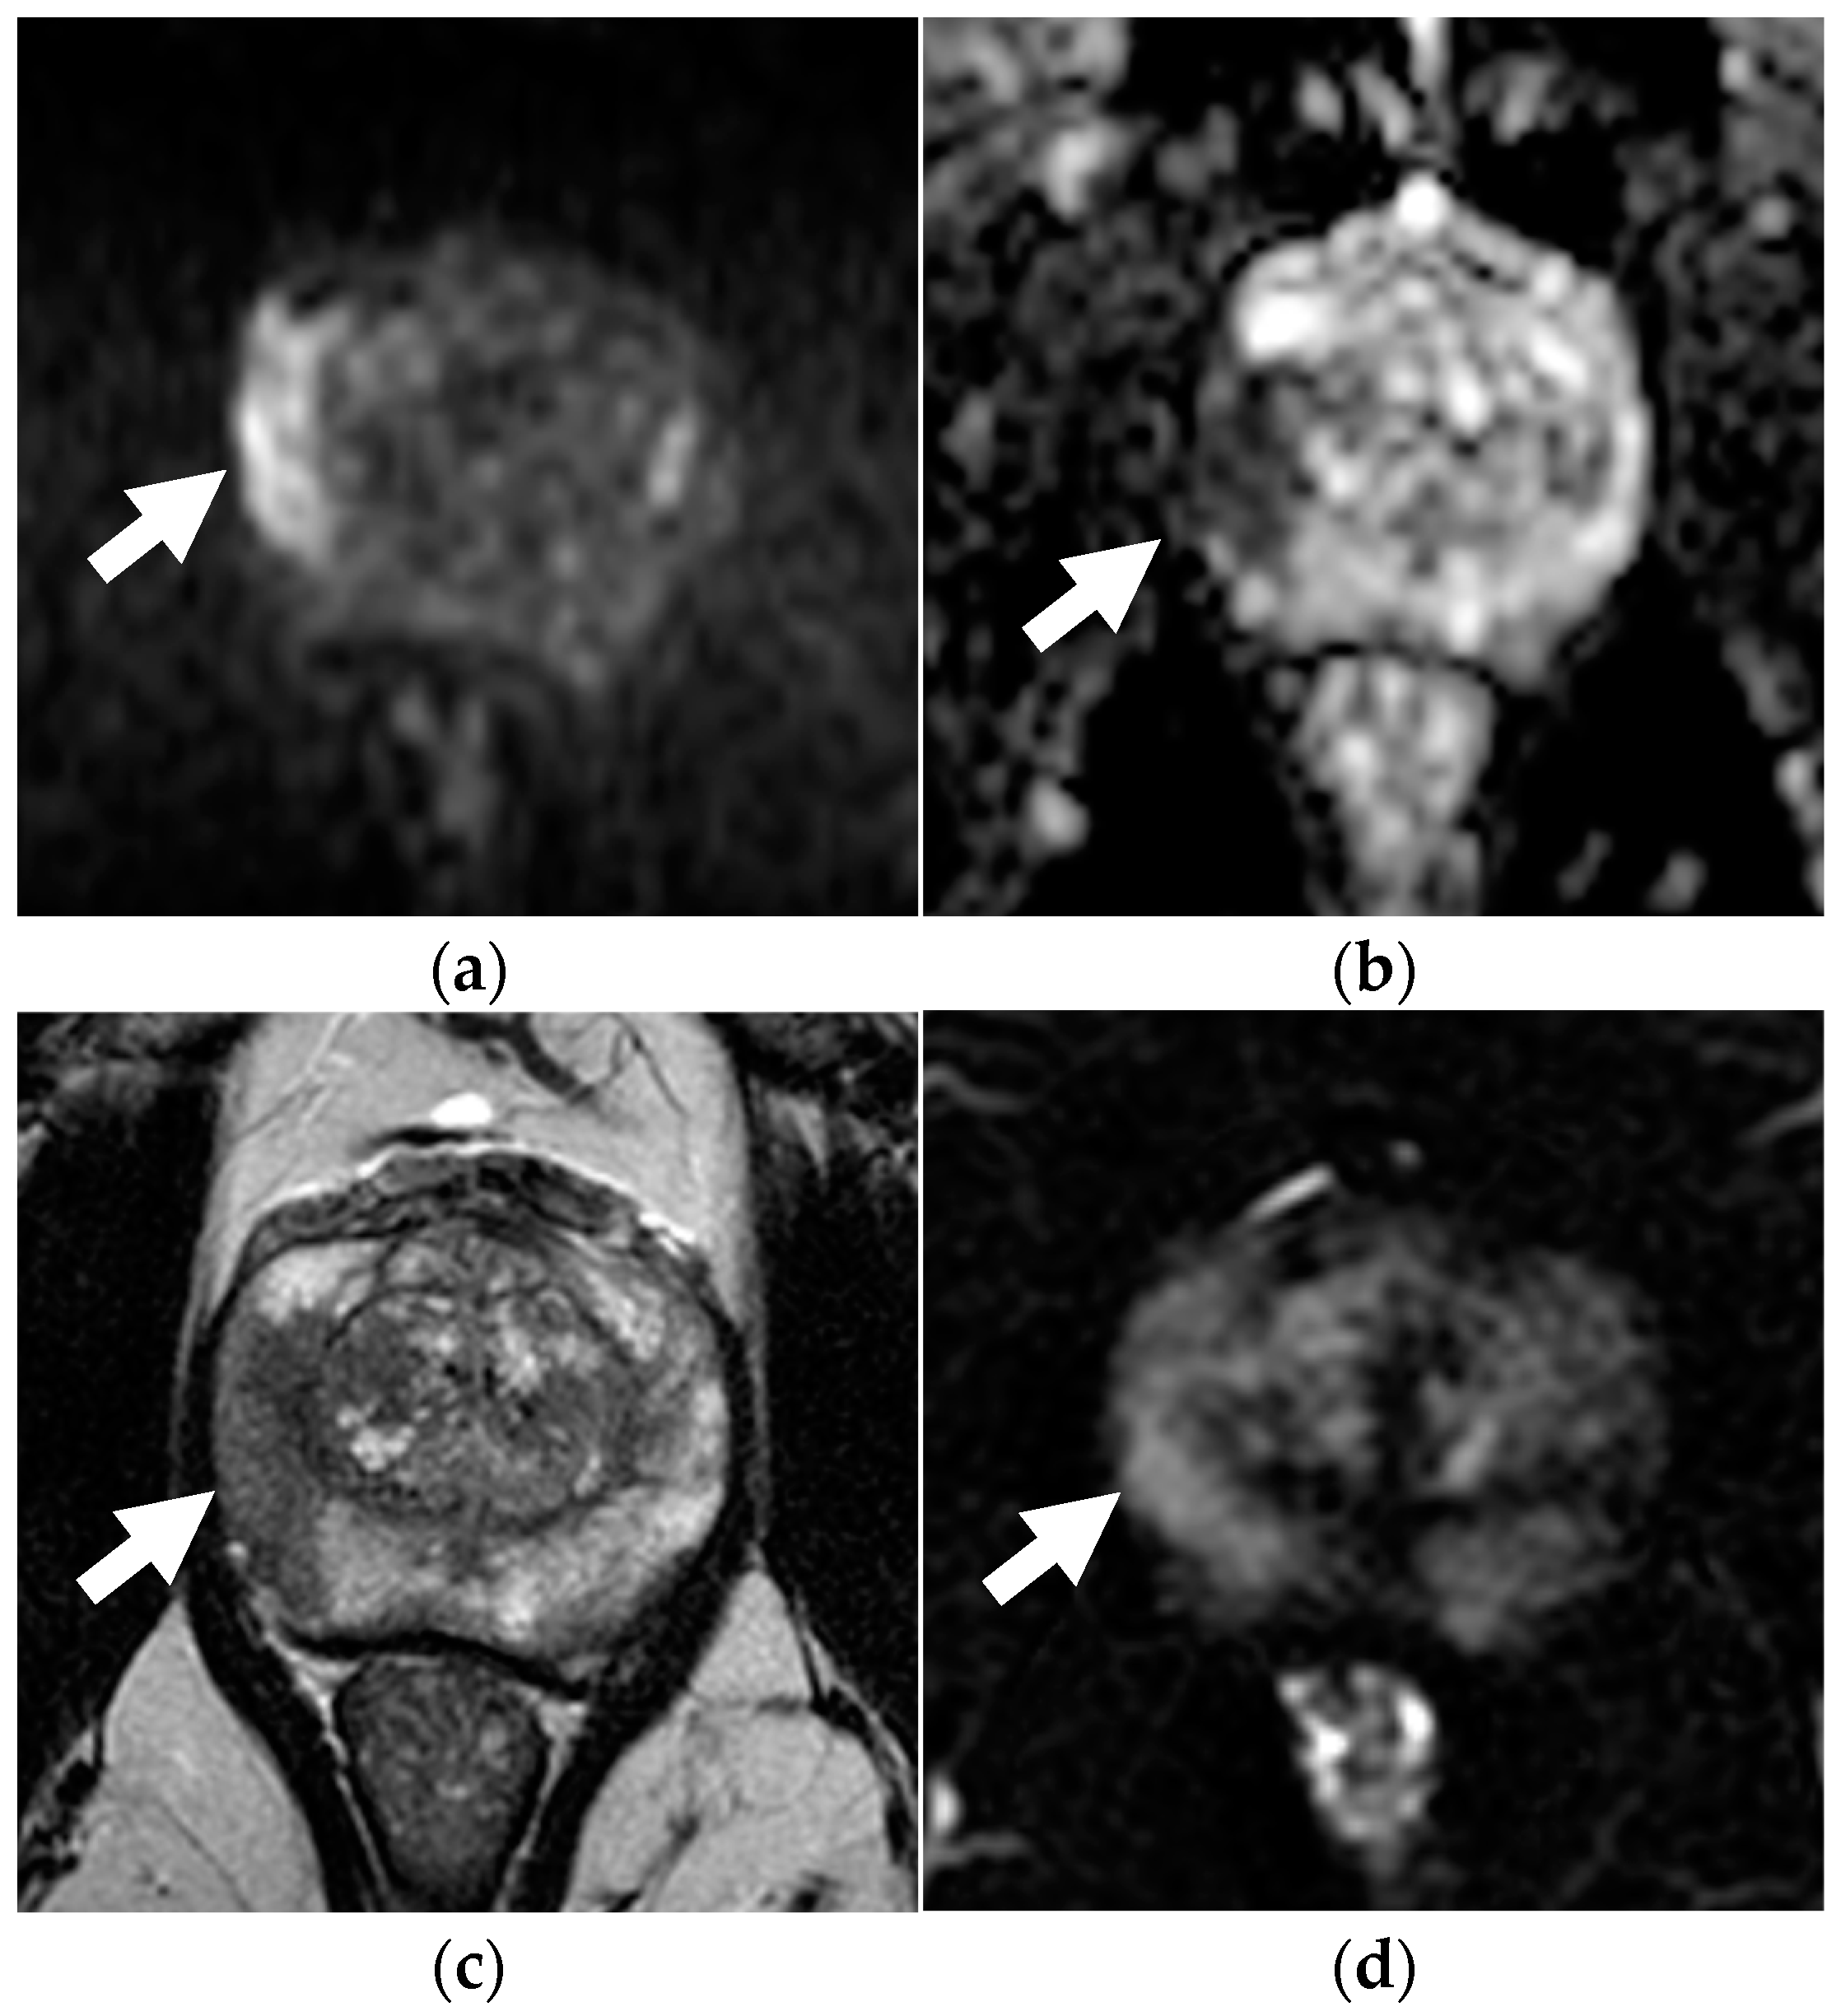

2.2. MRI Protocol

2.3. Image Analysis